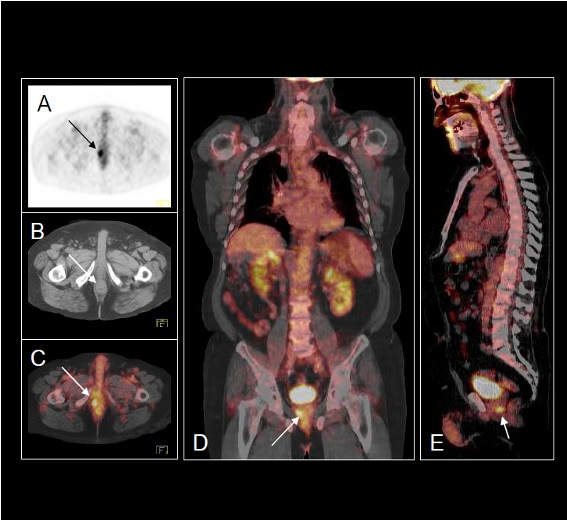

Se nos remitió el paciente al servicio de Medicina Nuclear para realizar una exploración PET-TAC con FDG. La exploración se realizó en un tomógrafo Biograph 6 (Siemens, Alemania) habiendo estado el paciente en ayunas (8h), hidratado (1 litro de agua) y mediante la administración intravenosa de 370 MBq de 18F-FDG. La adquisición de las imágenes comenzó después de un periodo de reposo de 50 minutos, rastreando desde las órbitas hasta el tercio medio de los muslos (4 minutos/cama). El volumen adquirido se reconstruyó por el método iterativo (4 iteraciones y 8 subconjuntos), con un zoom de 1 y en una matriz de 168. La corrección de atenuación se realizó con una fuente de rayos X incorporada al equipo y la adquisición de una imagen inicial por el método de modulación de dosis. En el análisis del estudio no se encontraron hallazgos sugestivos de recidiva local ni metástasis a distancia (fig. 1). No obstante, se descubrió un depósito focal patológico del trazador, de contornos bien delimitados y situación periférica en el lóbulo prostático derecho, de 12 mm de diámetro y elevada actividad (SUV 6,8), sospechoso de malignidad, que obligaba a proseguir investigando (fig. 2).

Con este resultado, se realizó una analítica de sangre en la que destacaba un PSA elevado (8,54 ng/ml; vn: inferior a 4,0 ng/ml) por lo que se remitió al servicio de urología para completar estudio. Se realizó biopsia y se confirmó la existencia de un adenocarcinoma de próstata con Gleason 7 (4+3). El diagnóstico final fue de un adenocarcinoma de próstata T1cN0Mx Gl7 (4+3), PSA <10 ng/ml.